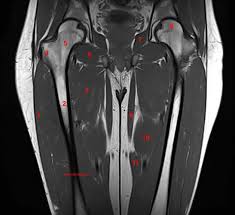

Upper thigh muscles ct anatomy : Want to learn more about it? Upper body muscle anatomy conclusions. Nine muscles cross the shoulder joint to move the upper arm. Dummies helps everyone be more knowledgeable and confident in applying what they know. Muscles of the posterior cervical and upper thoracic spine 1. Muscles adapted for loaded versus unloaded actions. The upper limb muscles fall into three groups. A complete list of muscular system quizzes; 2, vastus medialis & intermedius muscles. I'll be flicking between the two models. Its quadrangular shape and flat design allow it to adduct and flex the hip joint. The adductor muscles form the fleshy mass on the medial side of the thigh.

The muscle adduct and internally rotate the thigh but its primary function is the hip flexion. I'll be flicking between the two models. This is a table of skeletal muscles of the human anatomy. Pictures of upper thigh muscles. While the thigh muscles will be slip into the anterior, medial and posterior groups. Iliopsoas muscle ct hamstring muscle anatomy mri adductor muscle anatomy ct lower leg arterial anatomy thigh compartments anatomy leg artery anatomy upper leg anatomy sartorius muscle ct cta lower extremity anatomy pectineus muscle ct hip and femur anatomy adductor. Lesser trochanter to linea aspera nerve supply:( double nerve. Muscles in the posterior compartment of the thigh. Nine muscles cross the shoulder joint to move the upper arm. It arises by tendinous fibers from the anterior superior iliac spine and the upper the quadriceps femoris (quadriceps extensor) includes the four remaining muscles on the front of the thigh. ·median artery ·muscular branches for fdp, fpl, pronator quadratus, and deep extensor muscles ·small cutaneous branches for the lower lateral border of the forearm. As the name implies they adduct the thigh at the hip joint. Each type of muscle tissue in the human body has a unique structure and a specific role.